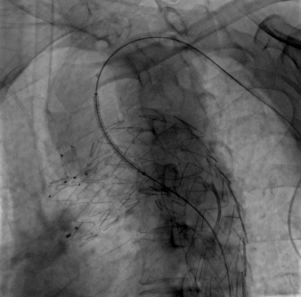

术前造影

患者平躺后,行全身麻醉,穿刺右侧股动脉、左颈总动脉与两侧肱动脉,经术前造影确认与术前CTA检查结果一致。

治疗车怎么推【弓部重建直通车】梅州市人民医院心内科团队运用Castor®分支型支架联合预开窗技术治疗主动脉弓动脉瘤合并迷走右锁骨下动_https://www.jmylbn.com_新闻资讯_第5张

术前造影(正位)